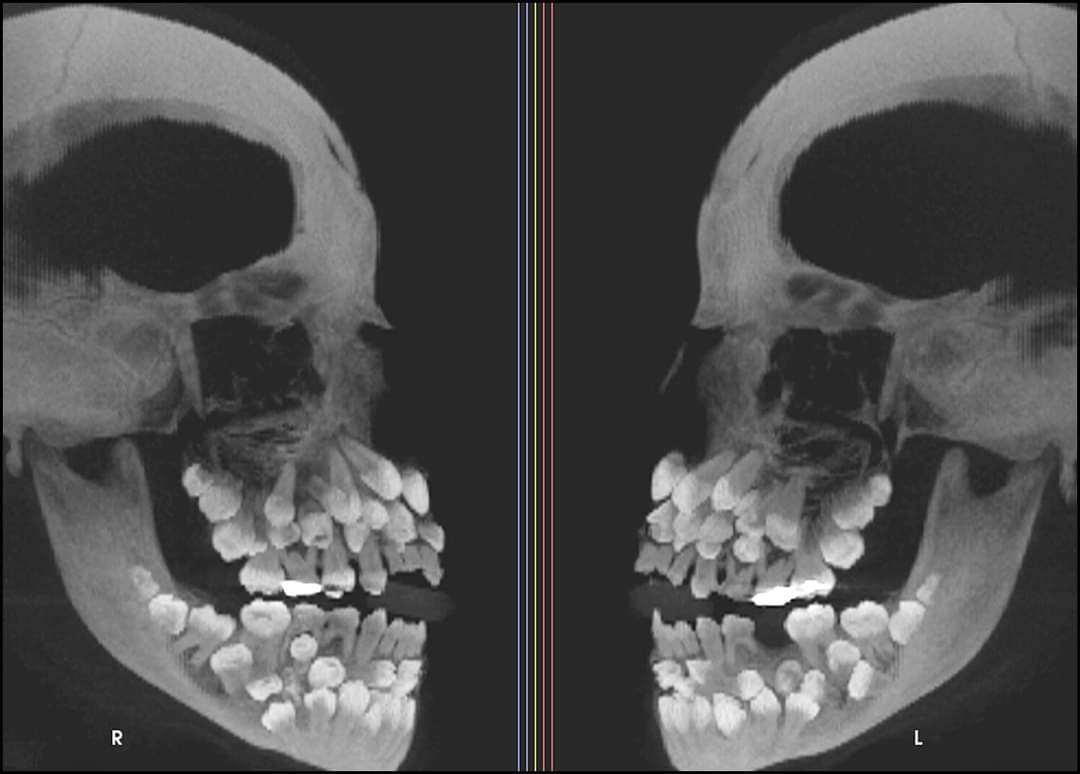

Hiperdoncia múltiple: un caso inusual. Una niña de 11 años y 8 meses acudió a la consulta; las radiografías mostraban 81 dientes: 18 caducos, 32 permanentes y 31 supernumerarios. (1/7) ⬇️

Una niña de 11 años y 8 meses acudió a la consulta; las radiografías mostraban 81 dientes: 18 caducos, 32 permanentes y 31 supernumerarios.